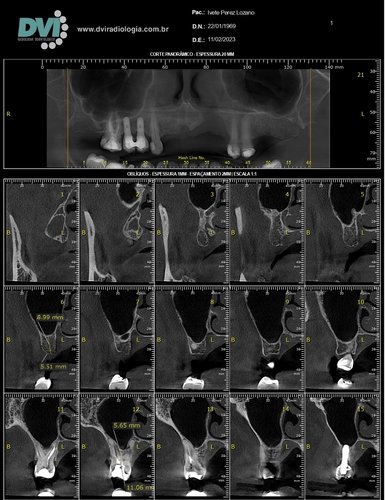

Passamos por vários especialistas e quando chegamos ao dentista da polícia militar, fomos informados que teríamos que fazer uma cirurgia para salvar o dente, cirurgia que durou em torno de 4:00 horas, mas infelizmente não foi possível salvar o dente e junto da perda do dente também tive uma perda óssea.

Tivemos que procurar um dentista para fazer um procedimento para colocar um dente, onde foi feito outro procedimento que usou os dentes das laterais, e sempre tive problema como esse outro que foi feito.

Procurando outro dentista, isso eu já mais velha, tentamos a opção de enxerto ósseo, onde meu organismo rejeitou, partimos para outra opção que eu podia fazer no momento, onde me encontro até hoje. Mas nesses dias perdi mais um dente e o restante amoleceu, e o resultado é a perda deles. Estou agora em desespero pois trabalho com crianças, falo bastante e quero muito realizar o procedimento chamado protocolo para me sentir segura ao falar, isso tem mexido bastante com minha autoestima e também a dificuldade para se alimentar, mas não tenho condição para isso, quero muito pedir a ajuda de todos(as), que sentirem de me ajudar.